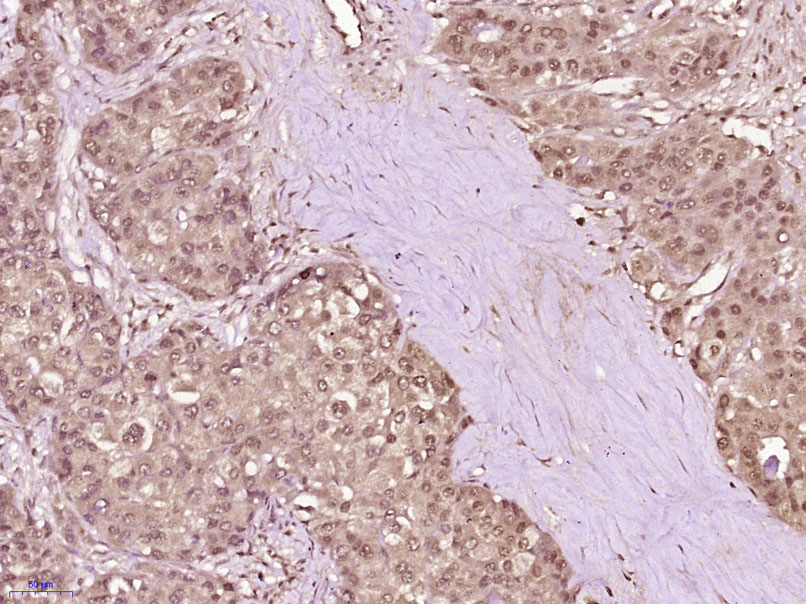

Paraformaldehyde-fixed, paraffin embedded (Human liver carcinoma); Antigen retrieval by boiling in sodium citrate buffer (pH6.0) for 15min; Block endogenous peroxidase by 3% hydrogen peroxide for 20 minutes; Blocking buffer (normal goat serum) at 37°C for 30min; Antibody incubation with (SNF2H) Polyclonal Antibody, Unconjugated (bs-12653R) at 1:400 overnight at 4°C, followed by operating according to SP Kit(Rabbit) (sp-0023) instructionsand DAB staining.

Paraformaldehyde-fixed, paraffin embedded (Human breast carcinoma); Antigen retrieval by boiling in sodium citrate buffer (pH6.0) for 15min; Block endogenous peroxidase by 3% hydrogen peroxide for 20 minutes; Blocking buffer (normal goat serum) at 37°C for 30min; Antibody incubation with (SNF2H) Polyclonal Antibody, Unconjugated (bs-12653R) at 1:400 overnight at 4°C, followed by operating according to SP Kit(Rabbit) (sp-0023) instructionsand DAB staining.